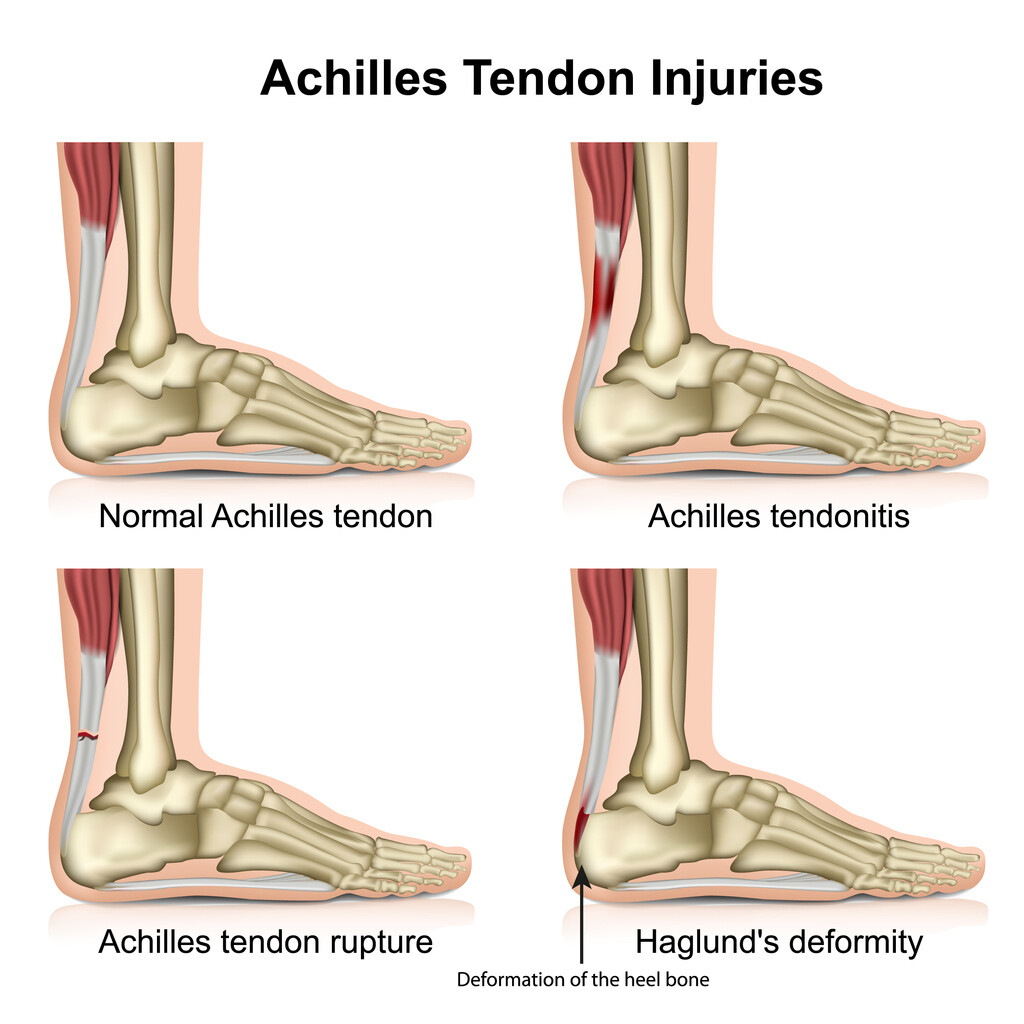

pictures of achilles tendon

Achilles Tendon Injuries – Active Care

Achilles Tendonitis Basics | Florida Orthopaedic Institute

Achilles Tendinitis Info | Florida Orthopaedic Institute

Achilles Tendonitis Basics | Florida Orthopaedic Institute

How Do You Know if You Have Damaged Your Achilles Tendon? | Pinnacle …

Achilles Tendon Rupture – Causes, Symptoms and Treatment | Bone and Spine

What is Achilles Tendinopathy? – Insoles and Orthotics – Healthy Step

Achilles Tendinopathy (Tendinitis and Tendinosis) – Complete Feet …

Achilles Tendinopathy | Mr Daniel Goldbloom | Melbourne

Achilles Tendinitis: Causes, Picture, Symptoms And Treatment

Achilles Tendonitis Causes, Symptoms & Treatment

Common Injuries of the Achilles Tendon – Osteopathy Singapore

Achilles Tendinitis – OrthoInfo – AAOS

Achilles Tendonitis / Tendonosis